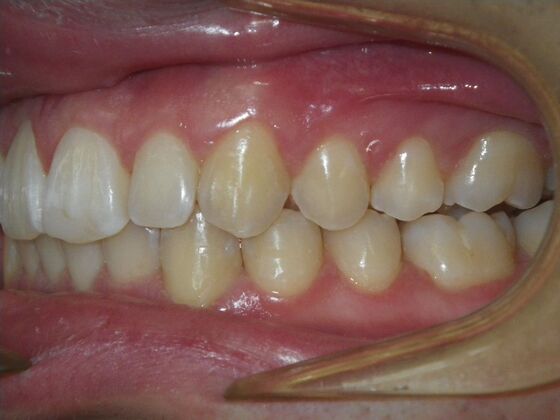

Patient presents with constricted upper and lower arches that will need expansion as well as slenderizing (IPR) to correct upper and lower anterior crowding.